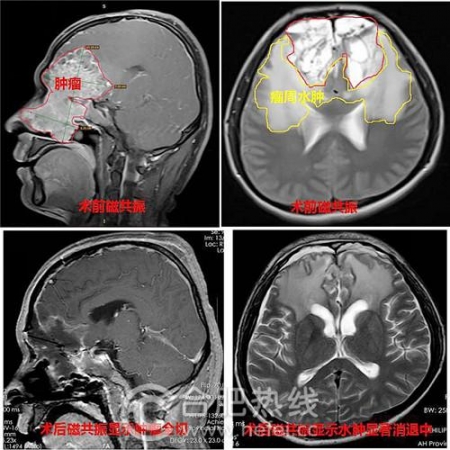

术前术后磁共振

术前,全国著名神经外科专家、安徽省立医院南区院长傅先明教授和神经外科主任牛朝诗教授主持了全科室专家对病情进行大讨论,并制定了详细周密的手术方案。神经外科颅底及脑干肿瘤外科亚专科主任夏成雨博士主刀,成功将鼻腔及颅腔肿瘤的全部切除,同时进行了颅底重建,防止术后脑脊液漏。手术耗时长达10个小时。术后,小刘没有发生脑脊液漏,顺利度过脑水肿关、感染关,恢复良好。

夏成雨主任介绍说,小刘的肿瘤是嗅神经母细胞瘤,是少见的鼻腔、鼻窦恶性肿瘤,在嗅神经分布区均可发生。小刘的肿瘤是目前遇到过的病情最严重的病例,肿瘤长达10cm,截止目前,国内文献也未报告过如此巨大的此类肿瘤。对于小刘的肿瘤,采用手术+术后放疗治疗是最佳方案。由于肿瘤巨大,还长入了双侧多个鼻旁窦内,造成了前颅凹底的骨质缺损,而且侵犯双侧额、颞叶,将主要动脉包裹。同时,由于患者经过放疗治疗,周围脑组织水肿,与肿瘤粘连,加大了切除分离难度。在切除肿瘤后,因颅底缺损较大,需要人工修复颅底,但修复后仍然容易发生脑脊液漏、颅内感染,危及生命。以上种种都给手术增加了很大难度,手术风险极大。